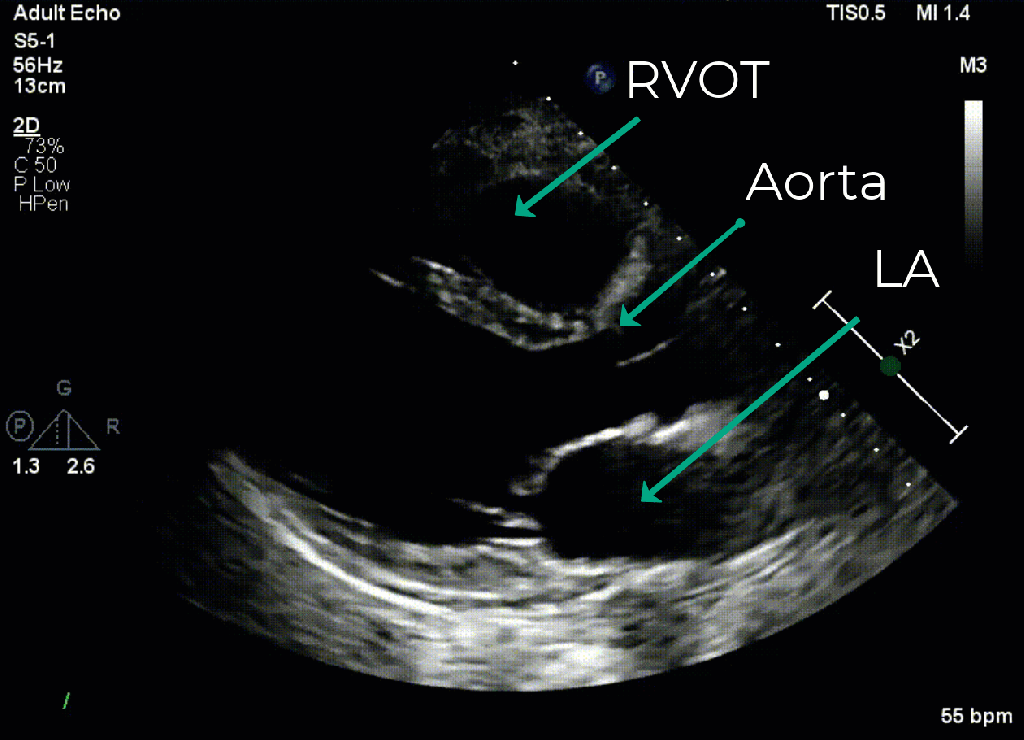

In the PLAX we really are only looking for the suggestion of RV dilation as little else can be gleaned given all we see is the RVOT in this view. The 2D measurement of the right ventricular outflow tract (RVOT) diameter from this view involves measurement of the lumen from the anterior wall of the RVOT to the septum at the level of the aortic valve during end diastole but this has been simplified into an approximation using the so called “rule of 1/3’s” where the relative diameter of the RVOT, aortic root, and left atria should be approximately the same. Therefore an increased ratio in favour of the RVOT suggests RV dilation as is shown in the clip on the right below.